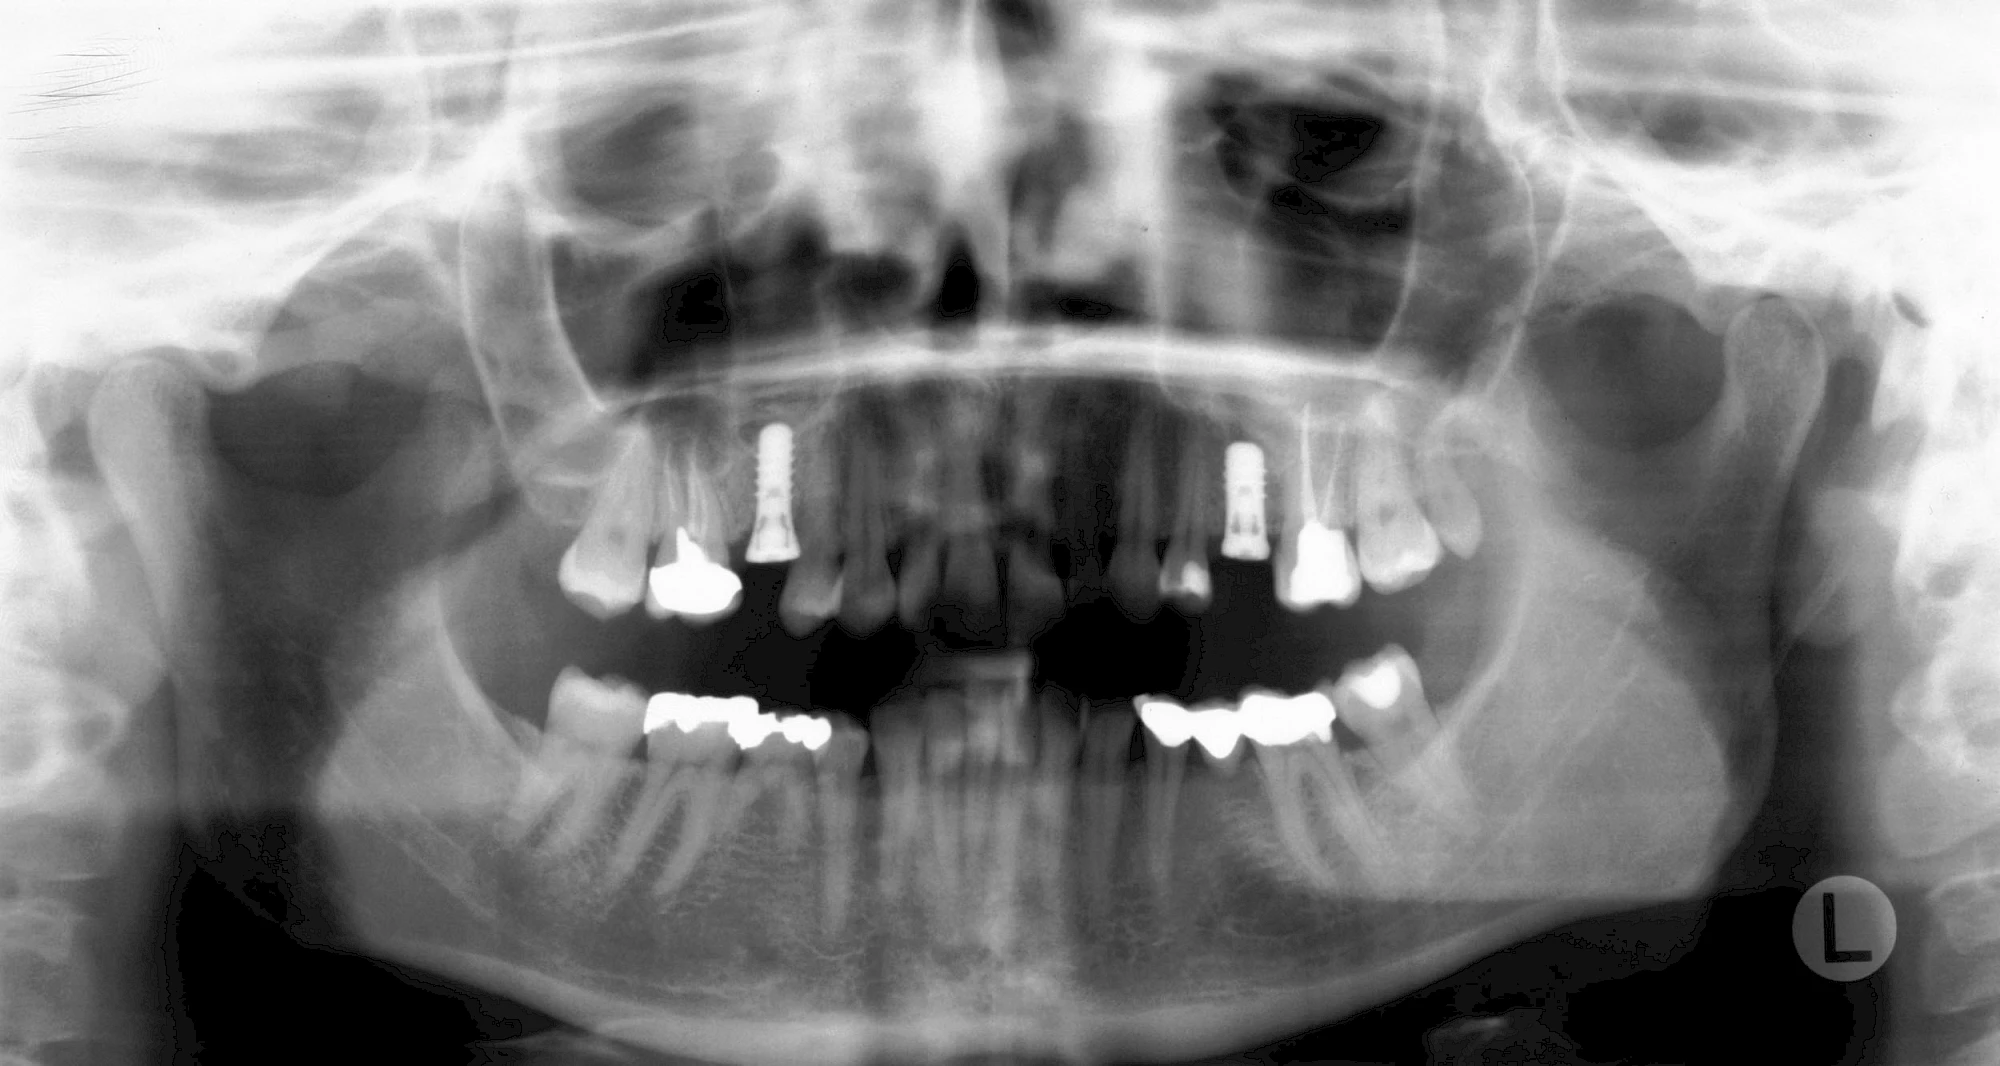

Damit Implantate an der richtigen Stelle im Kieferknochen platziert werden könen, gibt es heute vielfältige Möglichkeiten der Planung. In vielen Situationen kann die Erfahrung des Zahnarztes ausreichend sein.

Nicht selten ist jedoch auch eine technisch aufwändigere Vermessung im Vorfeld sinnvoll, z. B.:

- Wenn sich der Kieferknochen abgebaut hat

- Wenn der Nervverlauf im Unterkiefer beachtet werden muss

- Wenn die Ausdehung der Kieferhöhle im Oberkiefer beachtet werden muss

- Wenn wenige Restzähne keine gute Orientierung erlauben

In diesen Fällen kann die Planung mittels verschieden aufwendiger Röntgen-Techniken (Übersichtsaufnahme, DVT) ggf. unter Zuhilfenahme speziell angefertigter Planungsschablonen sinnvoll sein.